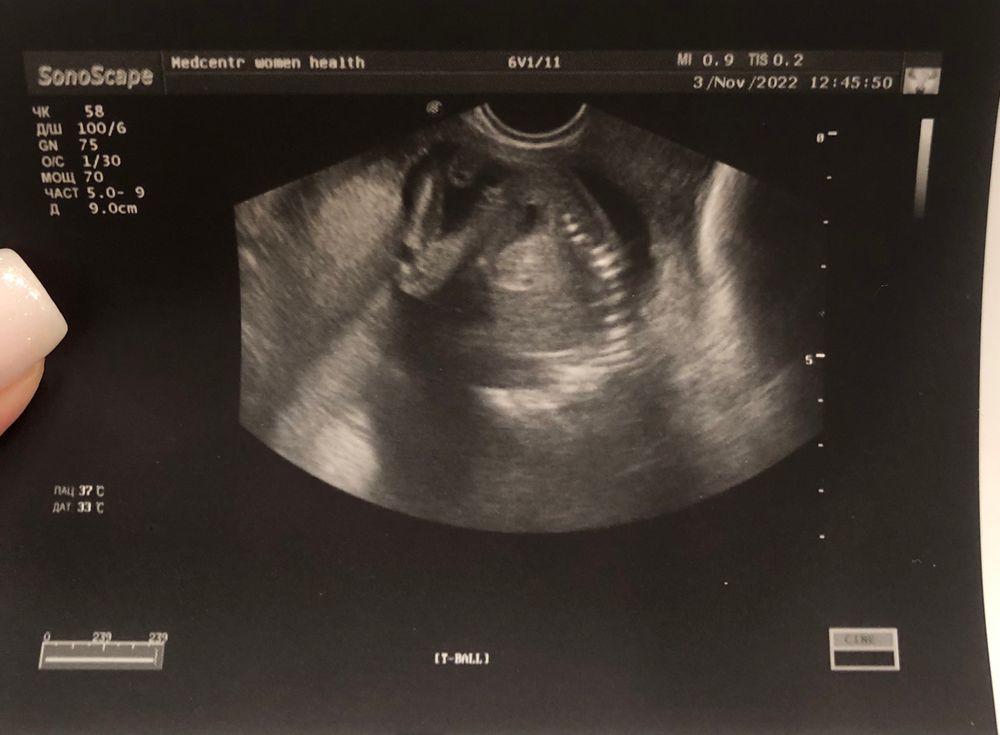

Наталья, срок 16,4 нед. Сказал, что она не понимает еще, для девочки что-то торчит, а для мальчика че то пока маленький совсем) девочки, это смешно, врач походу вообще не компетентный был, хотя ходила на платный узи.

А сколько тут недель? Но вроде не сильно торчит. Ставлю на девочку.

Я бы подумала,что мальчик...Странная врач))Не смогла просто ракурс поймать удачный))

В 16 уже точно врач должен был увидеть… переделайте у другого специалиста) я вчера была на узи,у меня 17, у моего парня уже хозяйство отчетливо видно было😁